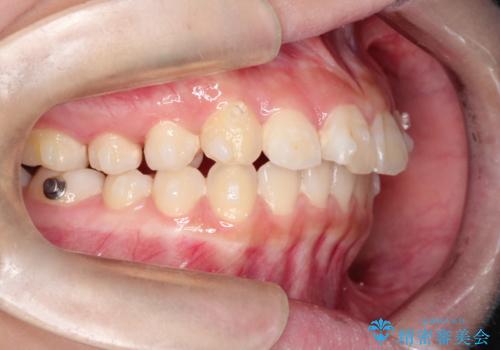

- 前歯が出ているのを主訴に来院されました。

上の前歯が前方に傾斜しており、上の前歯と下の前歯が接触していない状態でした。

上の奥歯を後方に移動させて、前歯を引っ込める計画としました。